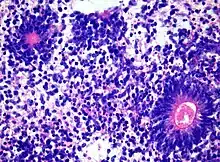

| Primitive neuroectodermal tumor of the central nervous system in a 5-year-old |

Medulloepithelioma, on the other hand, are tumors involving the constant cell division on the epithelium tissue where bundle of neuron endings are located.[1] Such tissue will differentiate into a similar form as the embryonic neural tube, also known as the starting structure of the central nervous system.[1][2][3] Medulloepitheliomas also present a pattern known as rosettes, characterized by the arrangement of a bundle of cells into circular shapes and around a center or a neuropil.[1] Ependymoblastoma also present rosettes as well as a higher density of cells.[1][3] It involves the process of differentiation into ependymal cells.[2][3]